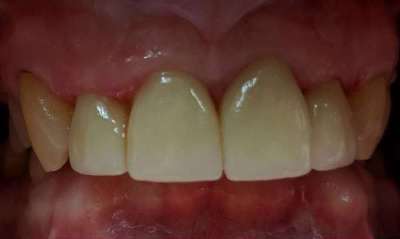

Crowns placed on front teeth to fix worn edges and darkening color of teeth. Crowns created harmony amongst the front teeth and gave the patient a more youthful smile.